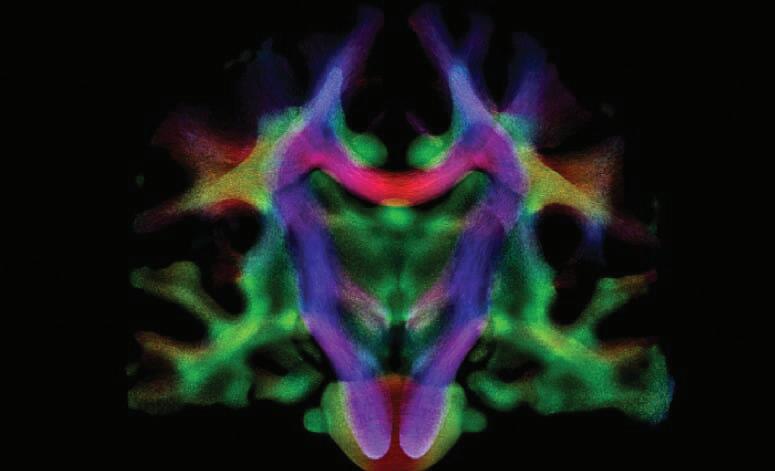

A photo of white matter, with its predominant orientation of fibers colored to reveal pathways traversing the regions, was a winner in the UW–Madison 2021 Cool Science Image Contest. Peter Ferrazzano, MD, professor and chief, Division of Critical Care, was one of the members of the research team that created the image using a magnetic resonance imaging (MRI) scan.